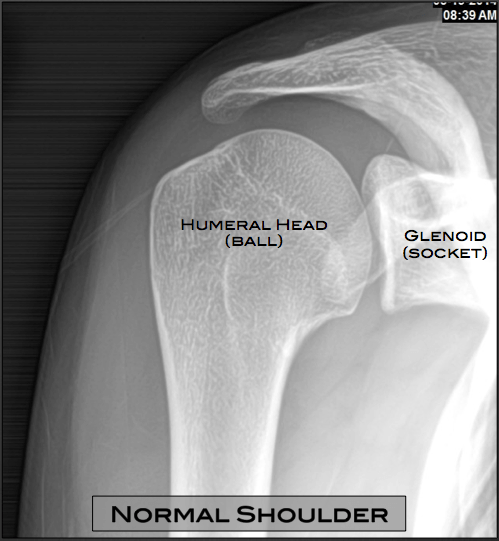

NORMAL SHOULDER 3 | buyxraysonline

Shoulder x-ray (AP)

Shoulder X-Ray AP View (con imágenes) | Fisiología

AP of the glenohumeral joint | Radiology schools, Radiology student …